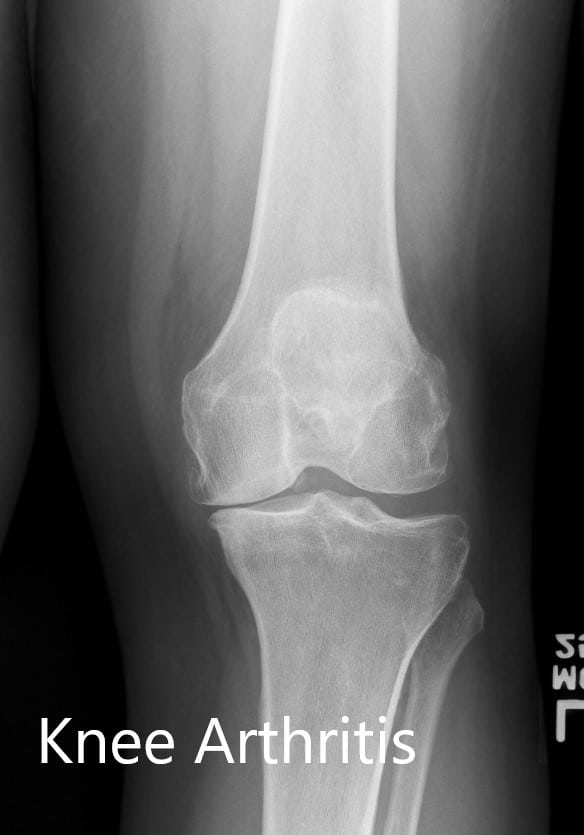

Los estudios de imágenes revelaron osteoartritis tricompartimental de la rodilla izquierda. Teniendo en cuenta el estilo de vida que limita el dolor de rodilla, se aconsejó al paciente que se sometiera a un reemplazo personalizado de rodilla izquierda. Los riesgos, beneficios y alternativas se discutieron con la paciente y su familia. Todos estuvieron de acuerdo en seguir adelante con la cirugía.

Radiografía preoperatoria de la rodilla izquierda que muestra AP y vistas laterales.